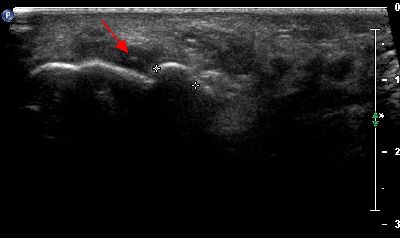

Base falange prossimale Modifiche anatomiche base falange prossimale

Sesamoidi Modifiche anatomiche sesamoidi